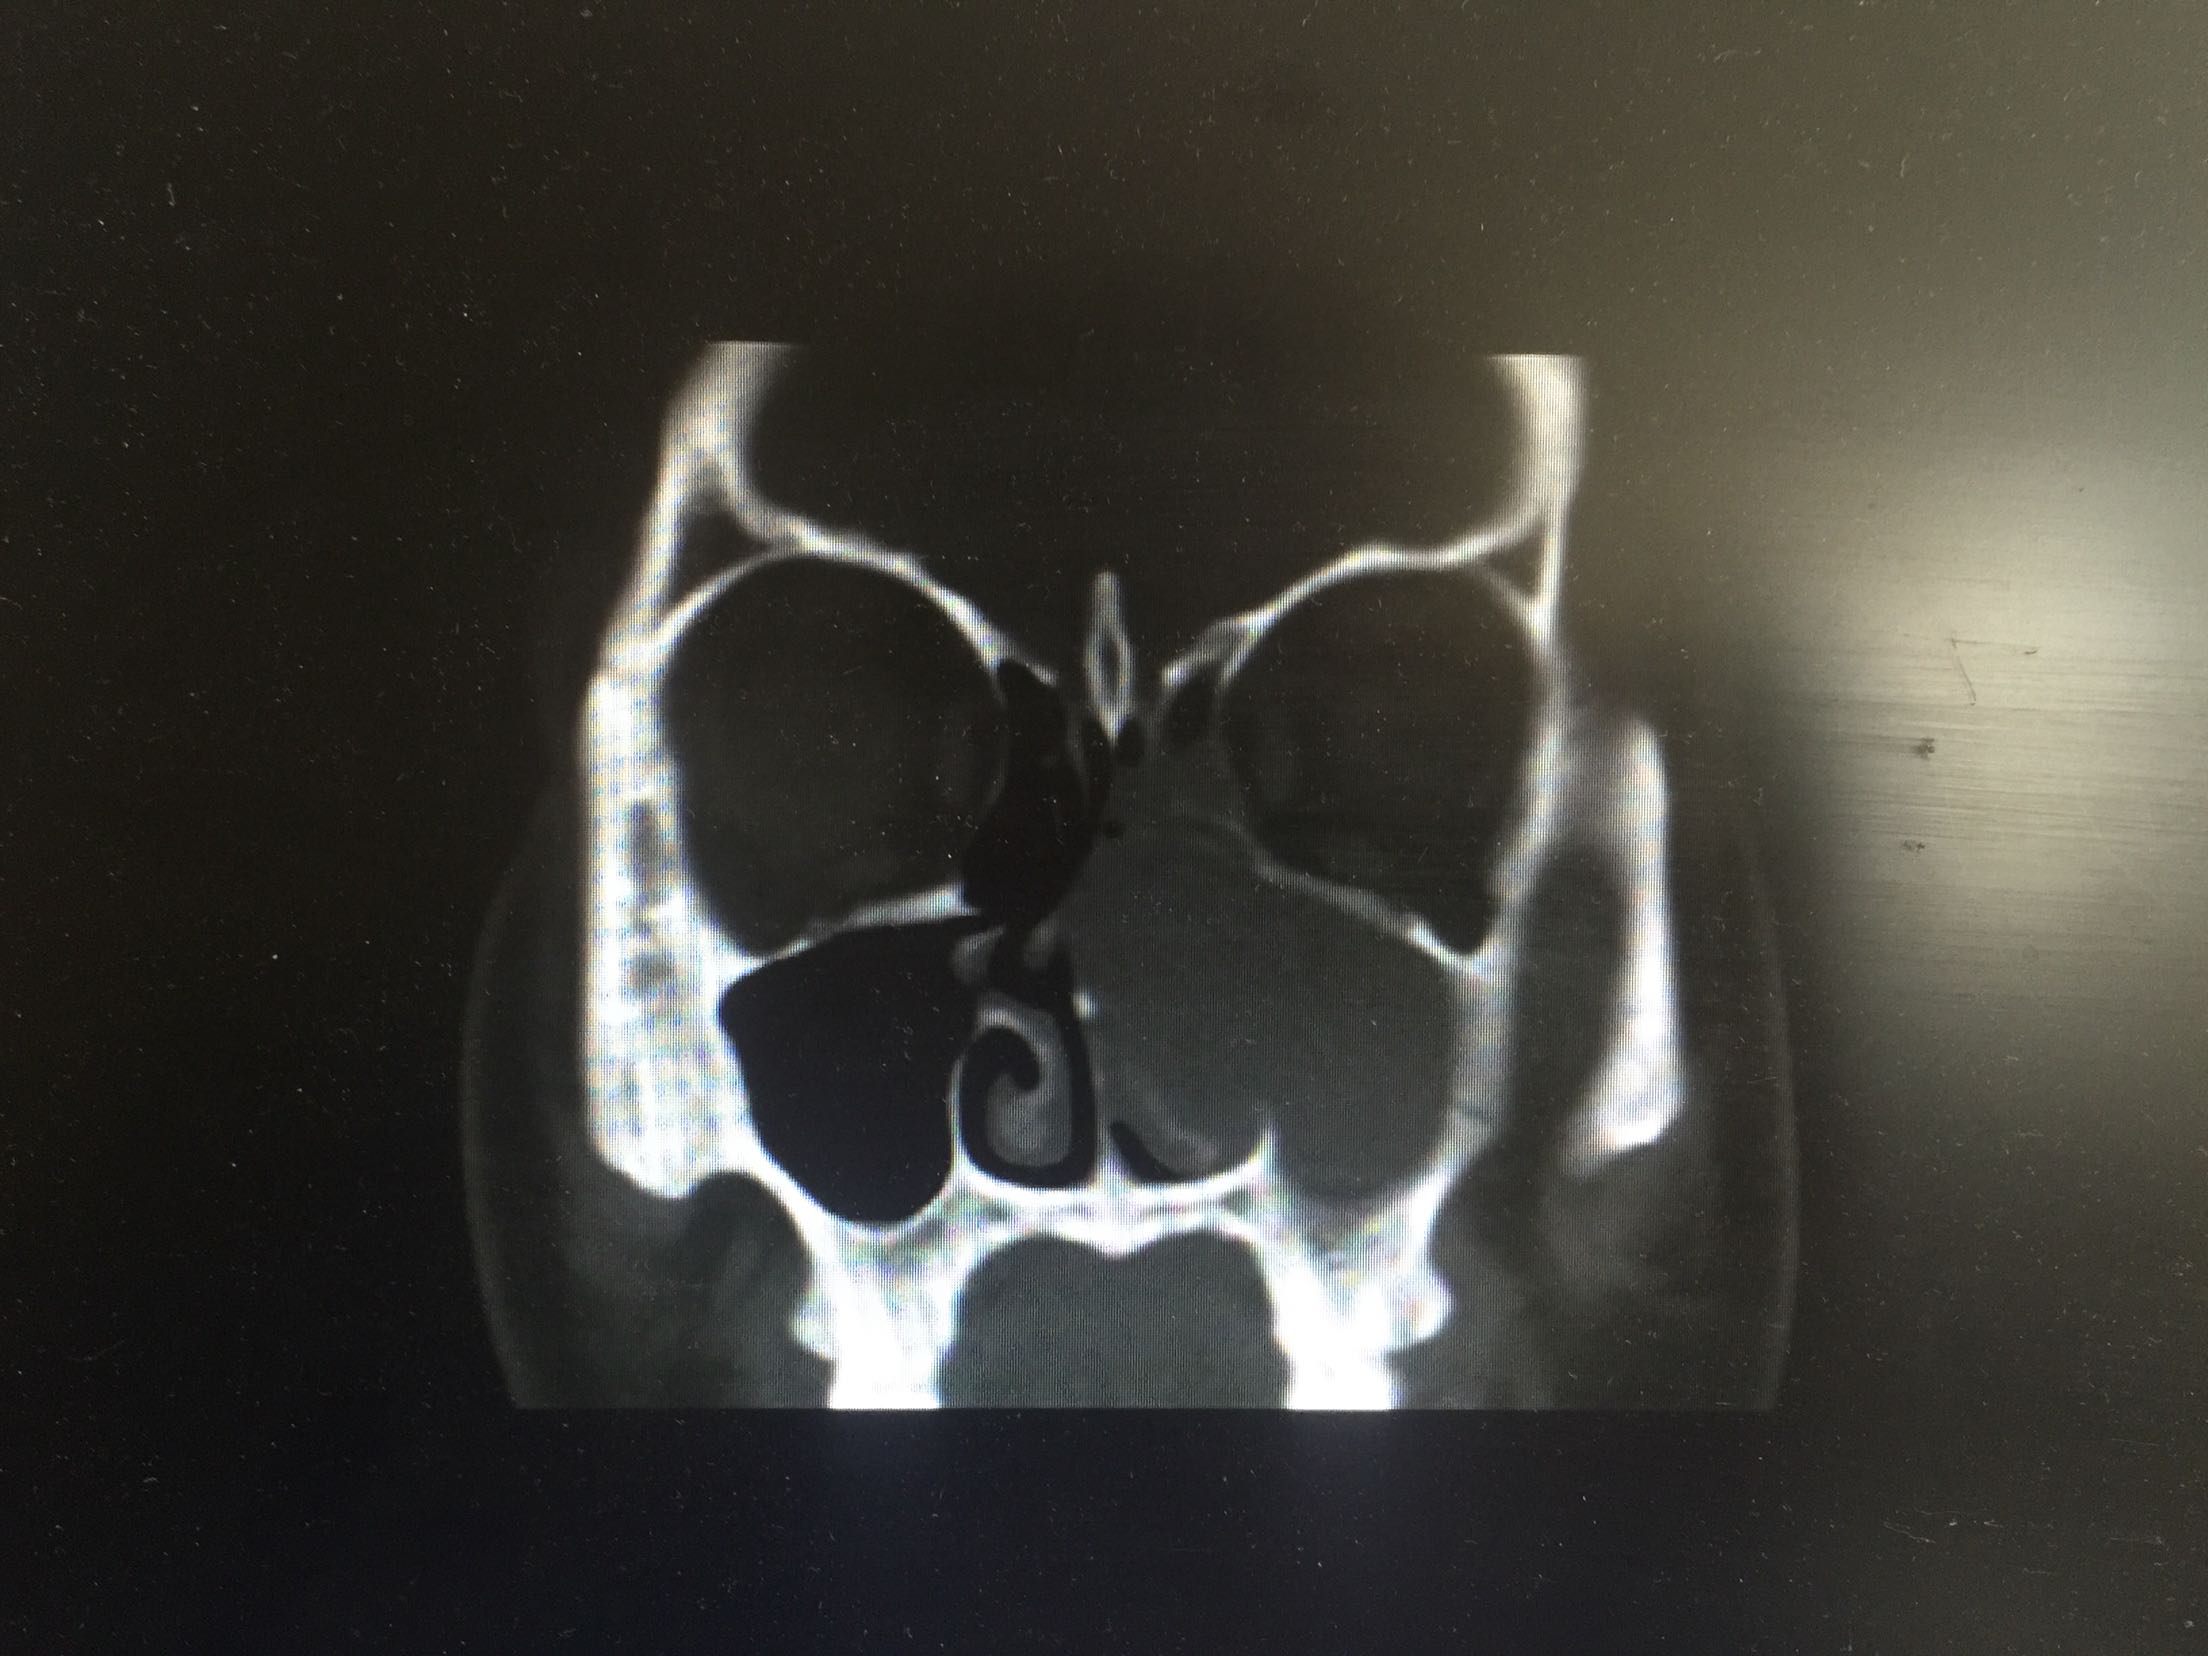

查体:鼻腔黏膜慢性充血,双侧下鼻甲、中鼻甲肥大。鼻内镜:左侧中鼻道可见少量息肉样新生物。鼻窦冠状位CT:左侧上颌窦占位性病变,不排除内翻性乳头状瘤。